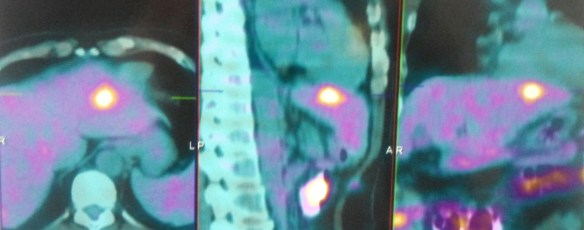

A PET scan showed:

- Two hypermetabolic metastatic nodules in the liver.

- No abnormal hypermetabolic foci or metastases elsewhere.